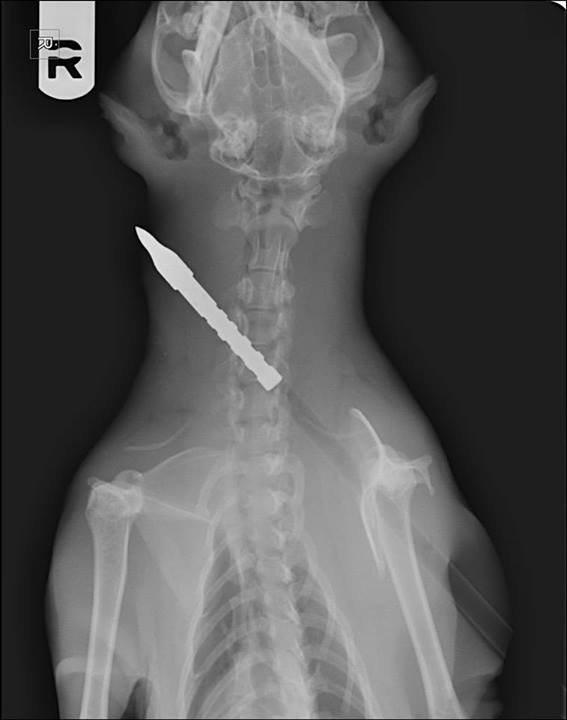

A full body lateral radiograph of the house cat Cat anatomy, Animals Does A Cat Have A Clavicle As many would have it, cats do not have clavicles. In this article, we will. A collarbone would broaden the chest, thus reducing the cat’s ability to get through. Well, it is clear from this guide that they indeed do. It allows flexibility, adaptability, and more. Explore the evolutionary origins of this bone structure and how it has been honed. Does A Cat Have A Clavicle.